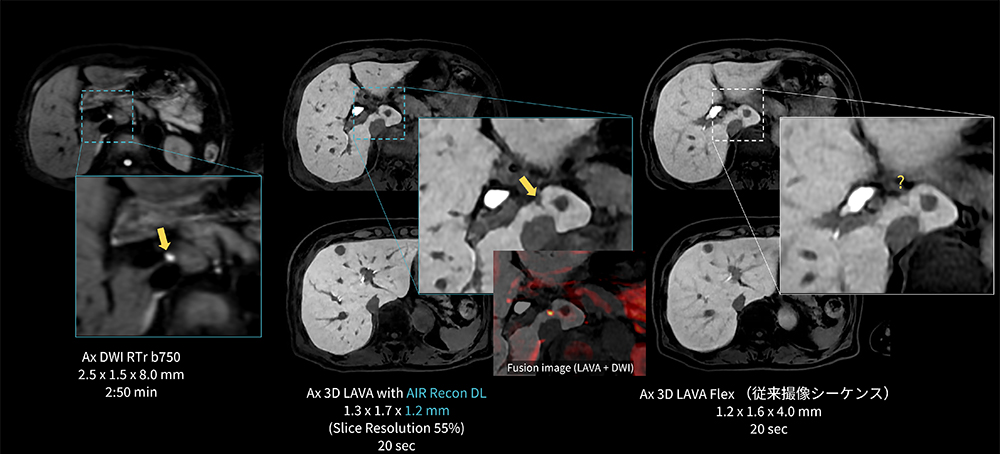

Case6 LAVA/上行結腸癌の多発肝転移

80代、女性。上行結腸癌の多発肝転移でEOB検査を施行。肝臓内に大小多数の結節が認められるが、S1に10㎜大と4㎜大の肝細胞造影相でのEOB取り込み低下あり。

4㎜大の病変(→)については従来撮像条件のLAVA-Flexでは描出が不明瞭であるが、AIR Recon DLを併用したThin sliceのLAVAではDWI高信号に合致した位置に病変が明瞭に描出されている。

MR30_Kariyatoyota_08.jpg図6 Thin slice LAVAを用いた上行結腸癌の多発肝転移における微小病変の描出能向上